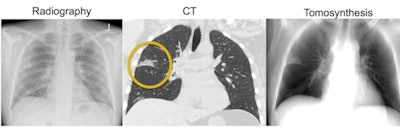

Tomosynthesis with digital radiography (DR) could be a useful tool for following patients with neutropenia for signs of fungal pneumonia. Researchers from the University of Washington said the technique could offer better performance than conventional x-ray without the radiation dose of CT.

Early detection of neutropenic pneumonia has been shown to reduce mortality, but the most commonly used screening modality -- chest x-ray -- has poor sensitivity, Edwards told attendees. CT has higher sensitivity but much higher radiation dose as well, which can be an issue when neutropenic patients are given weekly imaging studies to detect pneumonia.

Edwards and colleagues believe tomosynthesis could be a happy medium, with a lower dose than chest CT and sensitivity between radiography and CT.